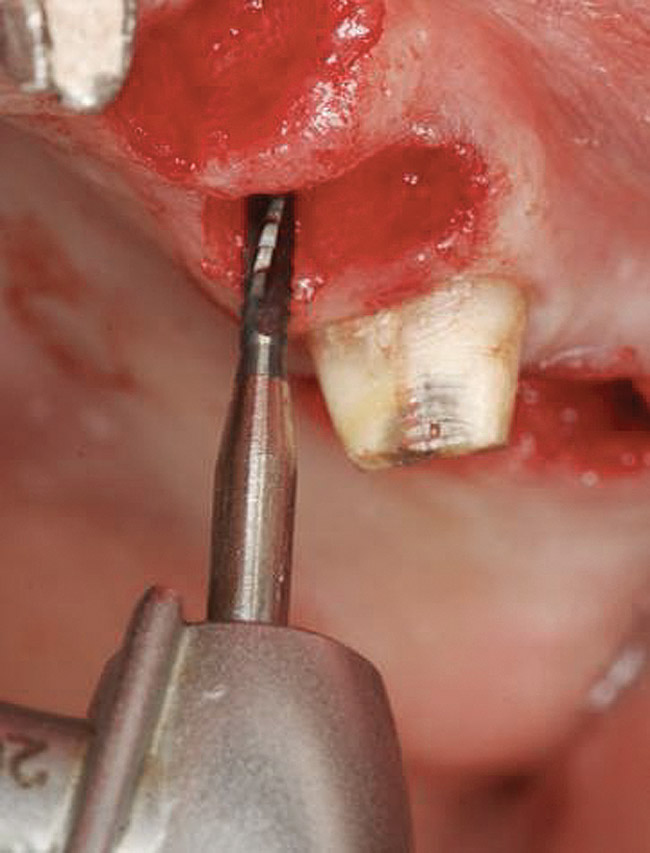

A round bur is usually used to mark the position where a 2-mm twist drill will be applied (Figure 1). Then the twist drill is employed to penetrate the cortical and trabecular bone (Figure 2). This provides information with respect to cortical bone thickness and medullary trabecular bone density. The amount of bone debris found on the twist drill can be interpreted as an indicator of bone quality (eg, the less debris and a more bloody appearance means softer bone). Four types of mineralized bone have been described by Misch (Table 1):1,2

When a 2-mm twist drill is used to full depth of the osteotomy (eg, 10 mm), it is difficult to change osteotomy angulation with a twist drill. If a correction is necessary, a side-cutting bur (eg, Lindemann) should be used (Figure 9). Furthermore, if there are doubts as to closeness of the osteotomy to adjacent teeth or vital structures, then a radiograph with a guide pin in place should be obtained.30 Ultimately, the angulation and location of the osteotomy should be consistent with design of the future restoration.31